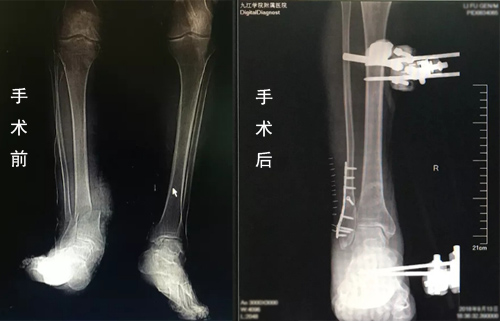

临床医学院/附属医院显微外科医护团队与麻醉科、手术室、输血科等进行了充分的术前讨论,制定好周密的麻醉及手术方案。由许刚主治医师主刀,赵斌副主任医师,赵庆飞、刘秭洋医师共同为患者实施了右小腿离断伤再植术。经过4个多小时的艰苦奋战,手术顺利完成小腿骨折、血管、神经、肌腱及皮肤的修复。术后由科室护理团队制定了详细的护理计划,严密观察患者生命体征及切口情况,全程进行细致护理。通过科室全体医护人员的共同努力,李大爷术后恢复各项指标良好。

据李军副主任介绍,断肢再植是一个体现医院显微外科能力的标志性手术。此患者受伤后断肢从表面上看有少量皮肤和肌肉组织将断肢与机体相联,但实际上这部分离断肢体已无血液供应和神经支配,已成为毫无活力的组织,这为再植手术的成功增加了难度;另外,老年患者的血管条件不好,是再植的又一个难点。此次手术用到了血管搭桥技术和神经束的吻合,手术难度系都数非常高,尤其是患者处于失血性休克状态,对医师的要求就更高。